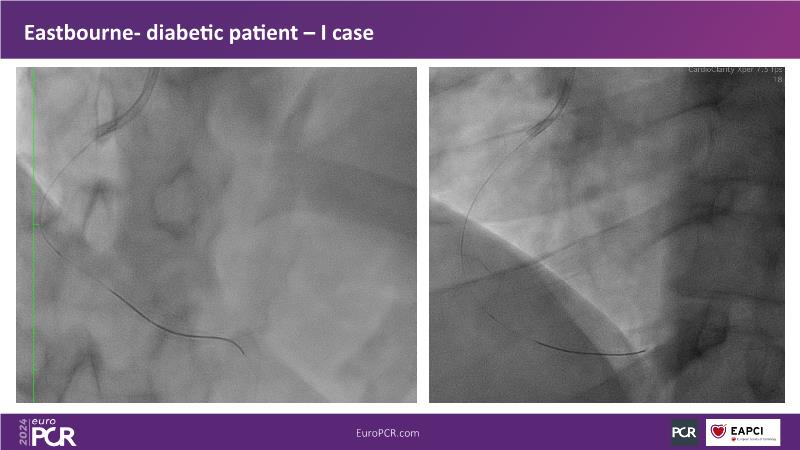

Browse this EuroPCR 2024 session to explore the safety and efficacy of sirolimus-coated balloons from pre-clinical data, review MagicTouch data from real-world populations with case-based examples, and learn about the MagicTouch sirolimus-coated balloon clinical programs. Discover insights and takeaways from the significance of the EASTBOURNE subgroups, and analyze the challenges and opportunities in PCI for diabetic patients.